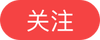

10岁女童下体渗液5年,医生竟从私密处取出金属球

儿童异物伤害中,最常见的是误食、误吸导致的消化道异物和气管异物,但还有一种很危险却常被家长忽视的泌尿生殖道异物,如女童阴道异物。近日,江西省儿童医院泌尿外科饶品德团队,成功为一名下体分泌物长达5年的10岁女童,实施宫腔镜操作在其阴道内取出一颗金属球,解除了孩子多年的痛苦。